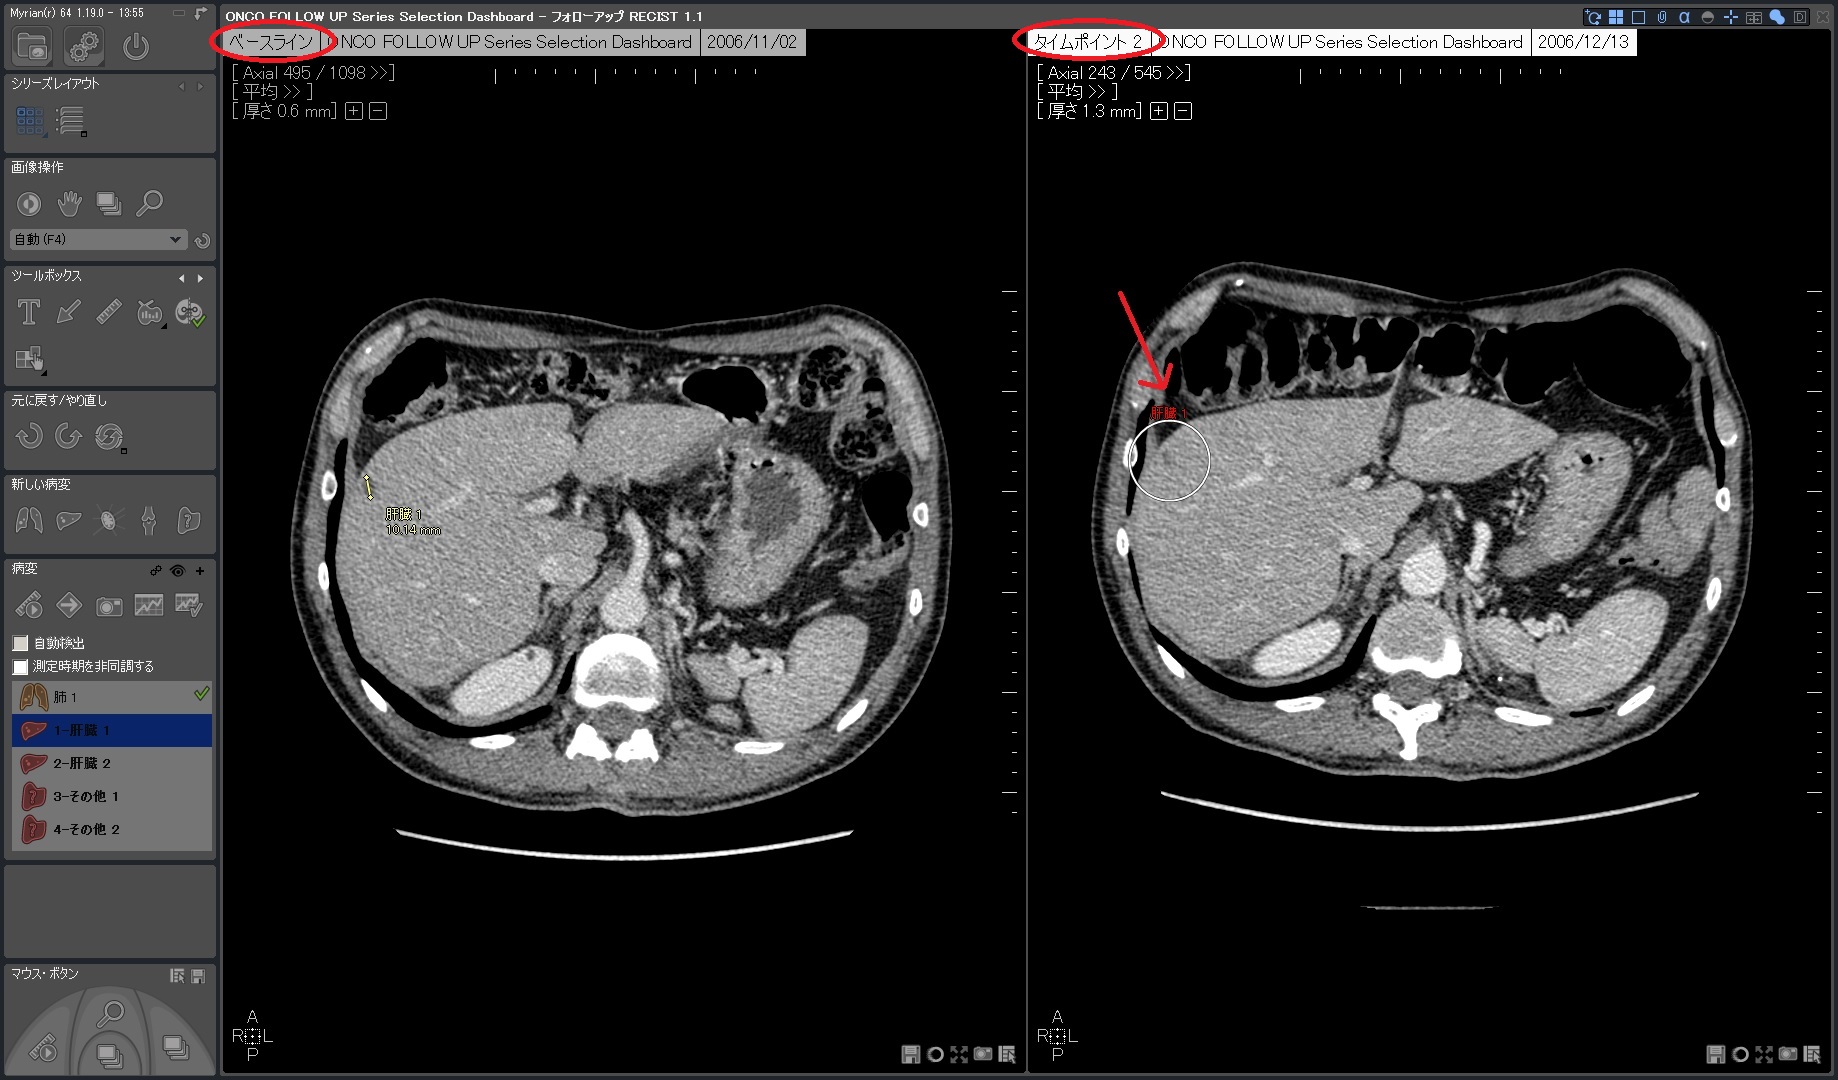

| 3.次のタイムポイントでは自動でロードされ、正確に位置合わせたROIを 素早く計測 |